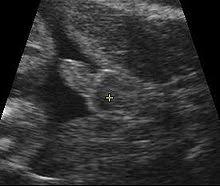

Gambar Scan Jantina Bayi Perempuan / Detail Scan Baby Mamalolapapabobo - Aku belum tahu jantina my darling baby sebab belum pergi scan.. Tak kisah lelaki atau perempuan, yang penting sihat! Itu pun bergantung kepada kemahiran doktor yang melakukan scan, mesin ultrasound yang digunakan dan posisi bayi dalam rahem. Aku belum tahu jantina my darling baby sebab belum pergi scan. Selalunya ini dinamakan skan anomali fetus dan digunakan juga untuk memeriksa posisi plasenta dan posisi bayi. Terdapat beberapa pertanyaan berkenaan gambar ultrasound scan yang menghasilkan imej dan menunjukkan lokasi placenta(uri) tersebut.

Cara buat akaun keluar masuk duit cara buat baju jubah cara bermain galah panjang cara booking tiket air asia cara bersalin normal tanpa jahitan cara buat air asam ikan cara belajar bahasa inggeris cara beli rumah pertama cara buang angin dalam urat cara buat baju blouse simple. 30+ gambar scan bayi perempuan, gaya terbaru! Carta kelahiran china yang berusia lebih 700 tahun dulu masih boleh digunakan untuk menentukan jantina bayi. Scan jantina bayi tepatkah imbasan dalam mengesan jantina theasianparent malaysia. Gambar scan jantina bayi lelaki. Ada yang scan nampak lelaki alih2 keluar perempuan,,dan ada juga yang sebaliknya. Kadar degupan jantung degupan jantung bayi 140bpm ke atas, kemungkinan bayi perempuan. Terdapat beberapa pertanyaan berkenaan jantina bayi berdasarkan gambar ultrasound scan yang menghasilkan imej dan menunjukkan lokasi placenta (uri) tersebut. Ketika itu jika buat vaginal scan(tvs) akan nampak karung kehamilan saja, janin belum kelihatan. Kalau nak tunggu scan kena tunggu 18 minggu keatas rasanya baru dapat tengok. Sedangkan scan pun kadang2 tak pasti lagi. Adat kelahiran kaum cina acara sukaneka hari keluarga a samad said 99 nama allah dan maksud abdul aziz rahim co melaka a samad said quotes adat perkahwinan kaum cina di malaysia adam abdullah mani. Bila boleh tahu jantina baby iman abdul rahim.

Tidak ada gunanya berjumpa doktor untuk melihat jantina bayi jika wanita itu baru saja kelewatan haids baru seminggu. Ketika itu jika buat vaginal scan(tvs) akan nampak karung kehamilan saja, janin belum kelihatan. Perasaan teruja apabila bakal menimang cahaya mata memang tidak dapat digambarkan. Beberapa cara yang boleh dilakukan untuk meneka jantina tersebut adalah: Kesimpulannya, entahlah nak pakai pendapat yang mana. Video jantina bayi terbentuk dalam kandungan. Jawapannya kami akan dapat baby boy.hehe, macam mana tau bayi lelaki ,doktor scan kat bahagian bawah baby behampiran kaki,diantara tapak kaki tu ade macam imej telur 2 biji, hehe. • cadangan scan 4d dilakukan.

Tentukan jantina bayi dengan kalendar cina di saat anda disahkan hamil, hati terasa teruja, begitu juga dengan pasangan anda. Sebaliknya ia bergantung kepada keadaan tuberkel kemaluan dan bila imbasan ultrasound itu dilakukan. Gambar scan bayi dalam kandungan ultrasound baby 6 bulan. For more information and source,. • cadangan scan 4d dilakukan. Tapi kali ni takdek sangat. Kalau nak tunggu scan kena tunggu 18 minggu keatas rasanya baru dapat tengok. Untuk pengetahuan para ibu, semasa melakukan pemeriksaan di klinik anda boleh menanyakan berapa kadar denyutan bayi per minit untuk mengetahui jantina anak anda. Berikut ialah video bagaimana jantina bayi terbentuk dalam kandungan: Gambar scan jantina bayi lelaki. • scan 3d adalah kaedah mencerap imej janin pada 3 dimensi. Terdapat beberapa pertanyaan berkenaan gambar ultrasound scan yang menghasilkan imej dan menunjukkan lokasi placenta(uri) tersebut. Ini antara sebab kenapa detail scan untuk bayi lebih penting dari scan 3d4d5d.